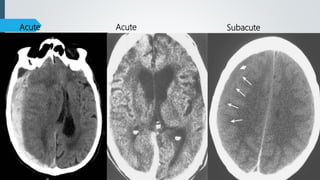

Age of SDH

 Hyperacute – upto 12 hours

 Acute – 12-48 hours

 Subacute – 3 days to 3 weeks

 Chronic – 3 weeks to months

CT Findings

 Hyperacute

 Heterogenous or hypodense

 Acute

 60% homogenously hyperdense

 40% mixed hyper-, hypodense with active bleeding (Swirl sign)

 Subacute

 Iso to hypodense

 GM-WM junction displaced medially

 Progression from hyper to iso to hypodense over nearly 3 weeks.

Acute SubacuteAcute

Chronic Acute on chronic